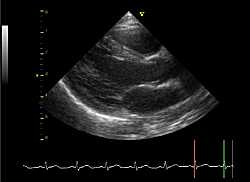

نعلم كافة النوادي الرياضية في كل الاقسام ان الفحوص الطبية المتعلقة بمخطط القلب

لم تعد اجبارية في بداية الموسم الرياضي لاستصدار رخص اللاعبين

لكن يبقى ايداعها اجباريا خلال الموسم لدى مكتب الرابطة